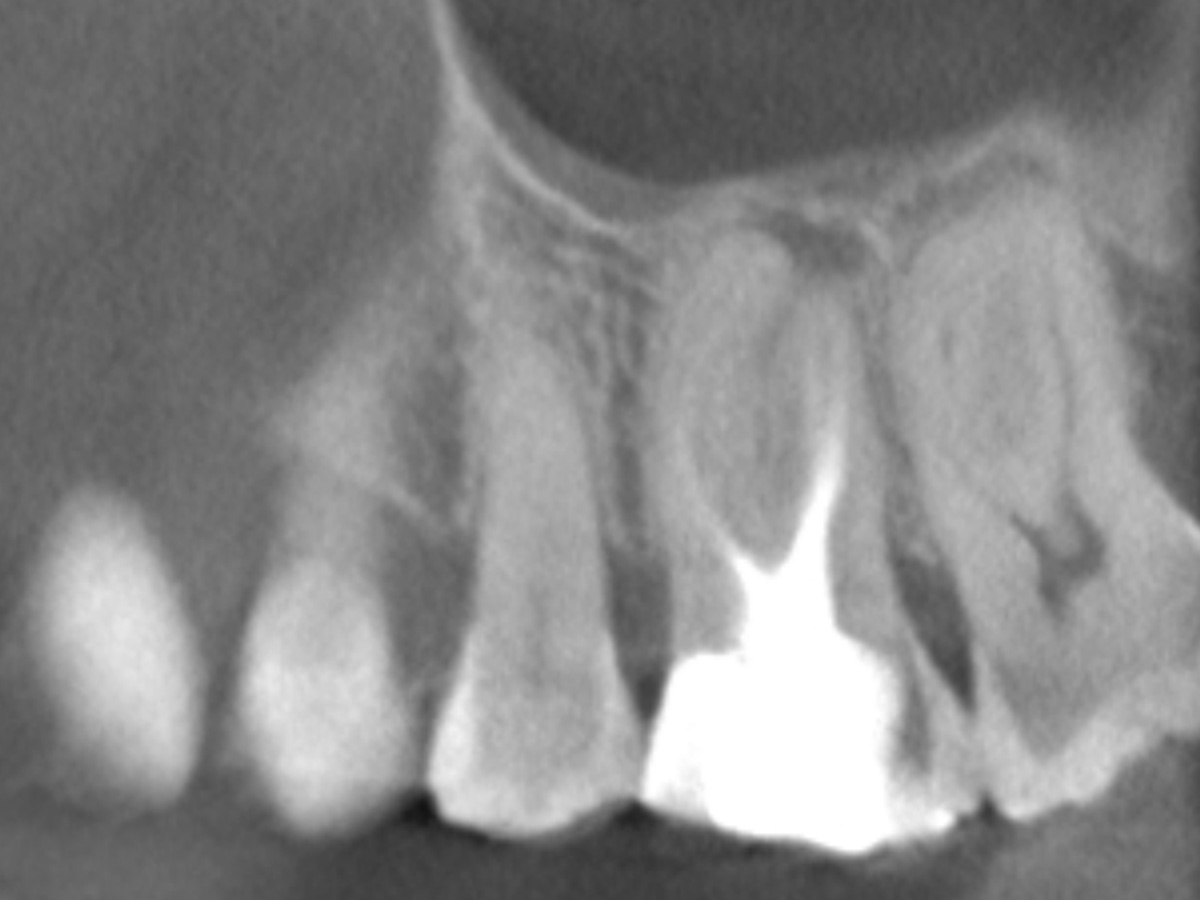

Obturation nach einer erfolgreichen Revision der insuffizienten Wurzelkanalfüllung mit einer symptomatischen apikalen Parodontitis

Der Patient stellte sich mit Aufbissschmerzen vor, wobei die klinische und röntgenologische Untersuchung eine symptomatische apikale Parodontitis an einem bereits wurzelkanalbehandelten Zahn 26 ergab. Die DVT-Aufnahme deutete auf einen unbehandelten zusätzlichen Kanal in der mesio-bukkalen Wurzel hin. Die Darstellung und Behandlung des mb2s sowie die Revision der bereits behandelten Kanäle erfolgte mit dem XP-endo® Rise Shaper bei einer hohen Umdrehungszahl von 2.500rpm.

Die Arbeitslängen der Kanäle wurden mittels elektrometrischer Messung bestimmt und die Kanäle aufbereitet. Alle Kanäle außer dem palatinalen wurden bakteriendicht mit einer Sealer-basierten Wurzelfülltechnik (Guttapercha und TotalFill® BC Sealer) verschlossen.

Für den ovalen Querschnitt der palatinalen Wurzel wurde eine warm-vertikale Technik angewendet. Dazu wurde der Guttapercha Hauptstift mit dem B&L Alpha und einem Hitzeplugger (55/.08) in der Tiefe abgetrennt und kondensiert.

Mit dem B&L Beta wurde der restliche Kanal nach der Backfill-Technik schrittweise mit erwärmter Guttapercha aufgefüllt. Die abschließenden Röntgenaufnahmen zeigen das Ergebnis, das mit den kabellosen Systemen präzise und effizient umgesetzt werden konnte.

Wurzelfüllung 26 exzentrisch

Abbildung 7

Wurzelfüllung 26 orthoadial